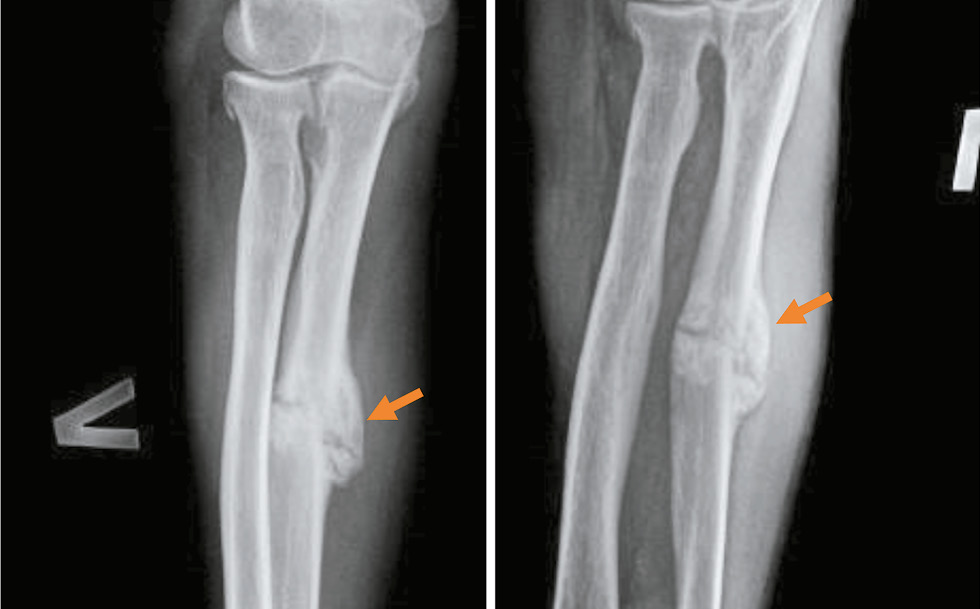

10) переломы давностью более года во всех наблюдениях имеют однотипные характеристики: линия перелома полностью закрыта, не просматривается, костная мозоль плотная, хорошо выраженная, равномерной интенсивности, с признаками перестройки костной ткани (см. табл. 3, 5; рис. 4).

Рис. 4. Перелом верхней трети диафиза малоберцовой кости давностью 16 месяцев (стрелка): линия перелома полностью закрылась, костная мозоль плотная, с чёткими признаками перестройки костной ткани.

Fig. 4. Fracture of the upper third of the diaphysis of the fibula, 1 year 4 months old (arrow): the fracture line has completely closed, the callus is dense, with clear signs of bone tissue restructuring.